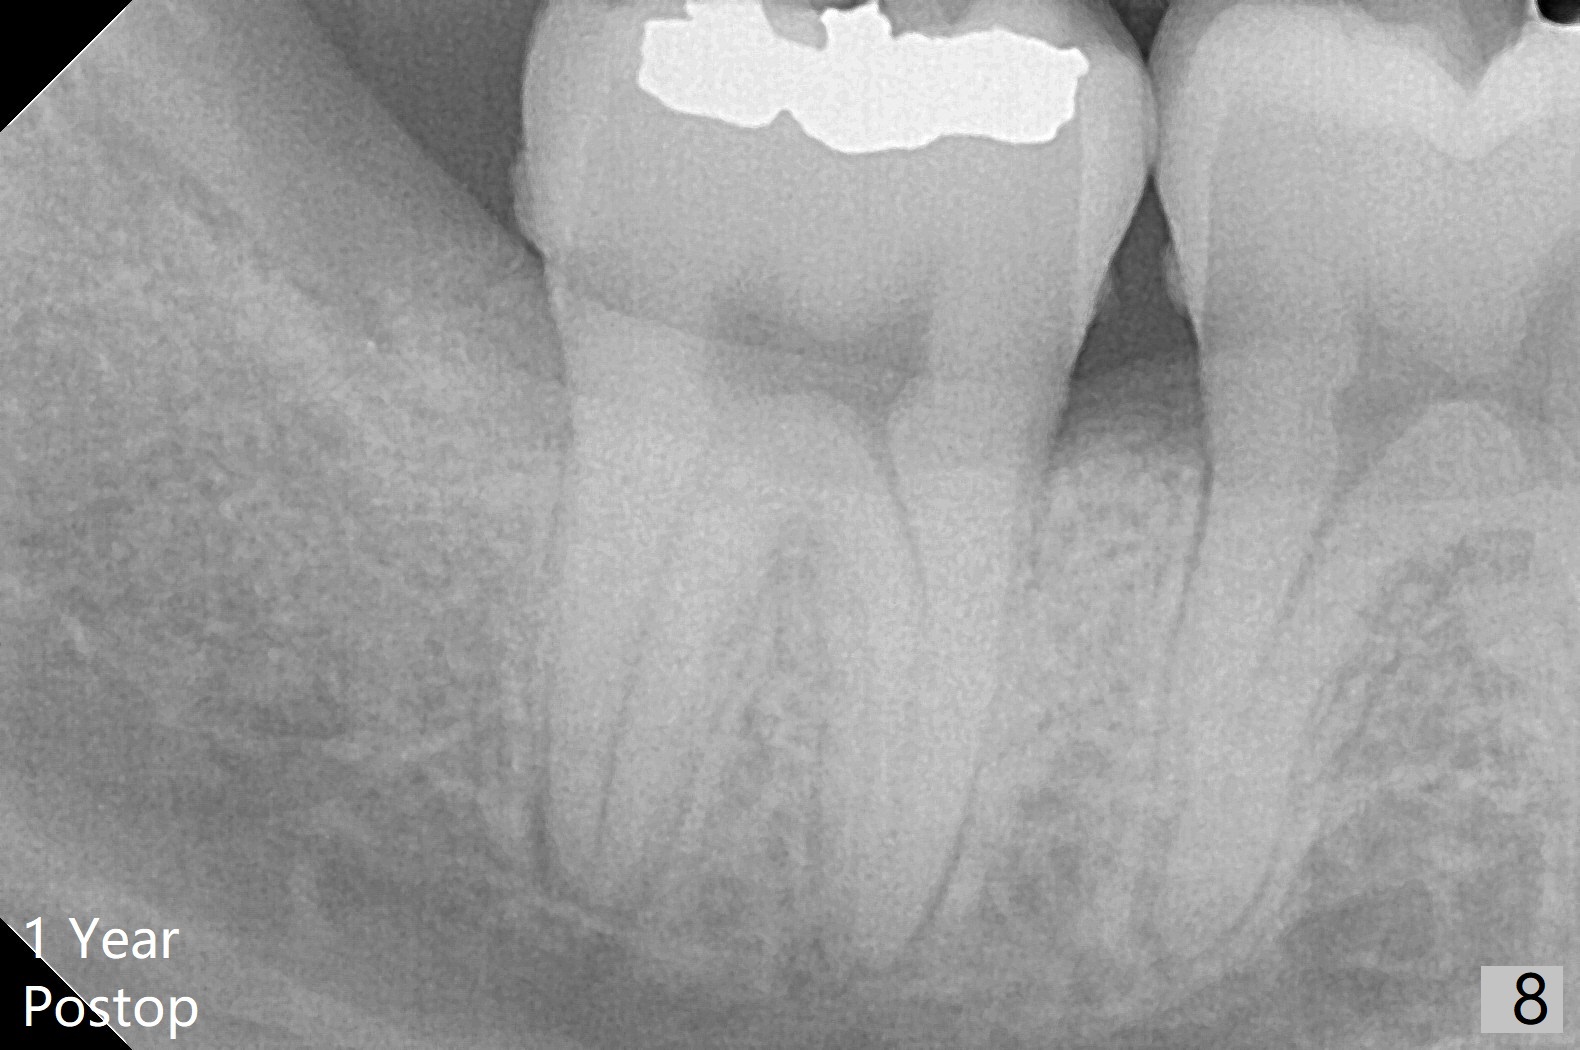

A 22-year-old man with poor oral hygiene requests extraction of the lower right 3rd molar. The buccal gingiva of the 2nd molar is erythematous and edematous (Fig.1 *). There is tenderness between #31 and 32 with severe bone loss (Fig.2 *). After extraction and debridement (Fig.3), Osteogen plug is inserted into radicular portion of the socket (Fig.4 white outline), while allograft is placed coronally (Fig.5, 7), covered by Collagen plug (Fig.6) before suturing. The bone fills the whole socket 1 year postop (Fig.8); there is no root surface exposure at #31. The bone fills the whole socket of #32 one year postop (Fig.8); there is no root surface exposure at #31.